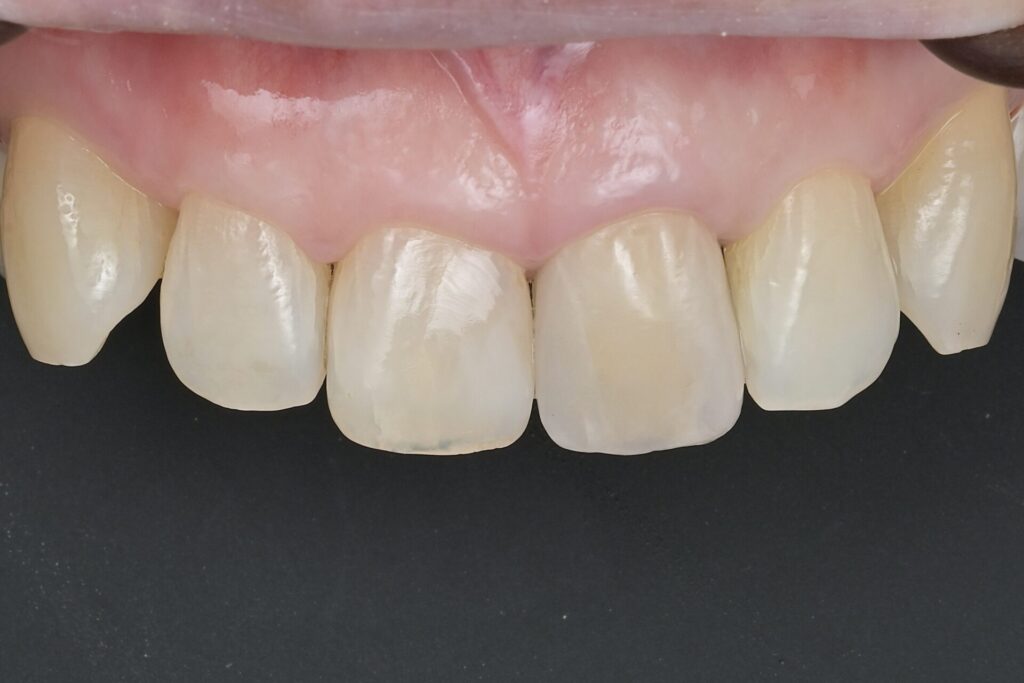

60代 審美治療 ジルコニアクラウン・虫歯治療 ダイレクトボンディング#55

Before

After

| 年齢 | 60代 | 治療方法 | ジルコニアクラウン/ダイレクトボンディング |

|---|---|---|---|

| 性別 | 女性 | 通院回数 | 6回 |

| 主訴 | 前歯を綺麗にしたい・歯を削る量を少なくしたい | 費用 | 308,000円(税込) |

| 治療のメリット | 歯を削る量を少なくできる・自然な見た目・境目がピッタリできる | ||

| 治療のデメリット | 大きい虫歯治療には適応できない場合がある | ||